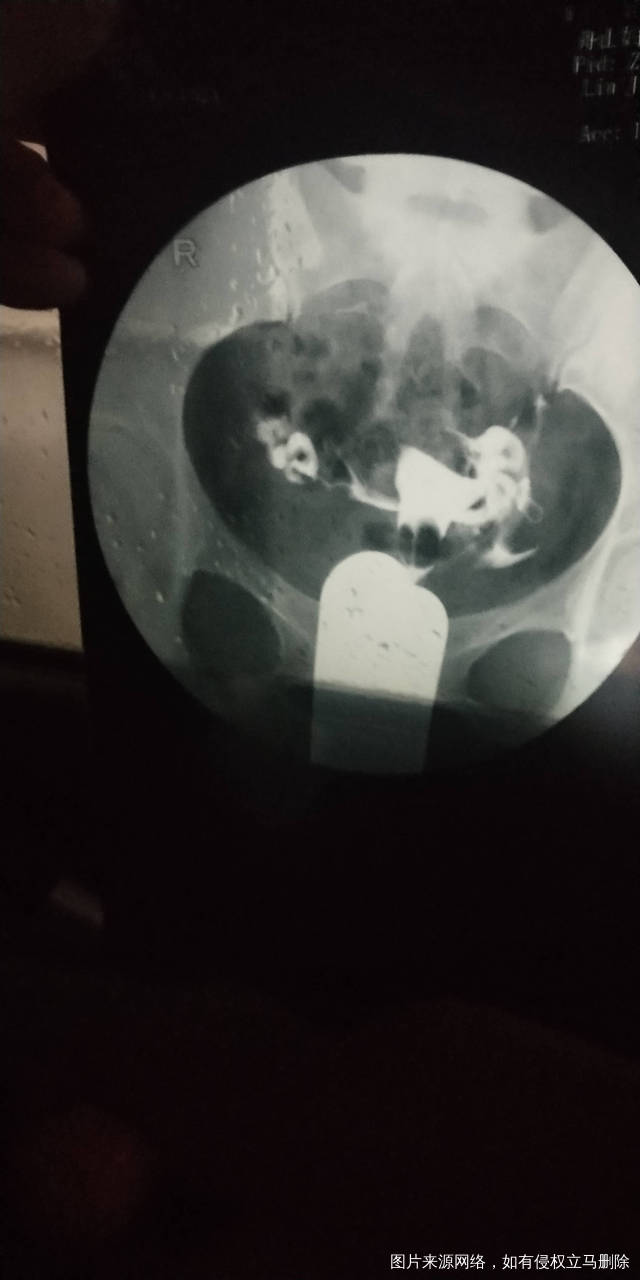

做完输卵管造影第六天了小腹还是感觉沉甸甸的如

可以热敷腹部,如果有发热,腹痛加剧,白带量多,有异味,随时就医